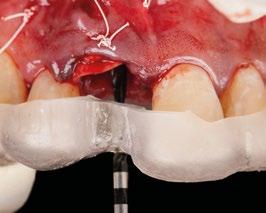

8.- Realizamos osteotomía mediante férula quirúrgica utilizando fresa piloto. (Figuras 22 a 24)

9.- Seguimos preparando el lecho utilizando fresado biológico con la OsseoShaperTM. (Figura 25)

10.- Colocamos implante Nobel Biocare N1TM TiUltra de 3,5x13. (Figura 26)